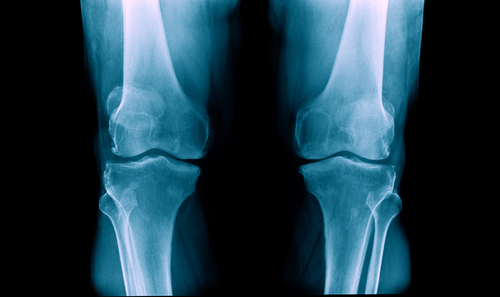

Youngsters who smoke may be at risk of developing low bone density -- a condition that may lead to an increased risk of developing osteoporosis, experts say.

"Smoking has a negative effect on the bones, causing loss of bone mass and, eventually, premature osteoporosis when young people take up smoking," Raju Vaishya, Senior Orthopaedic Surgeon, at Indraprastha Apollo Hospitals, said in a statement on Wednesday.Smoking as a habit typically begins in high school or the college years, when bones are still developing. It also interferes with calcium and vitamin D absorption in the body.

Besides, in the case of a bone injury, a person who smokes is more likely to have a longer period of recovery and greater risk of complication, doctors noted."Smoking during the years of bone-building puts you at risk of osteoporosis in the later stage. Smoking after 30 will speed up the loss of bone mass almost twice as faster," Vaishya added.Smoking kills over one million people in the India annually, according to The Global Adult Tobacco Survey (GATS) India report. The economic burden of tobacco consumption is around Rs 104,500 crore per annum.

In a study, recently published in the journal Annals of the American Thoracic Society, smoking was found to be an independent risk factor for low bone density among both men and women.Each additional pack-year of smoking raised the odds of having low bone density by 0.4 percent. The participants with normal bone density had an average of 36.6 pack-year of smoking, while those with low bone density had an average of 46.9 pack-years of smoking history.